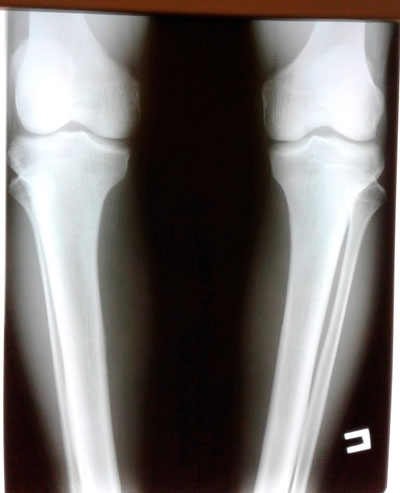

Дата операции - 10.07.2019г.

Дата снятия аппаратов - 01.04.2020

Срок сращения - 9 месяцев.